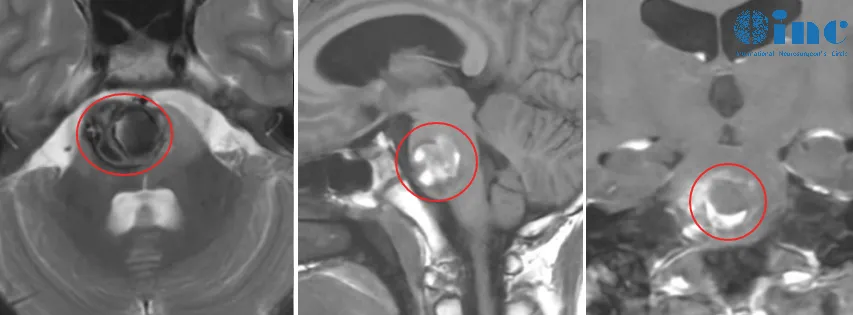

我儿子12岁那年,因为频繁头痛恶心,我们带他去了一趟医院。没想到磁共振一做,医生告诉我们孩子可能是海绵状血管瘤。病灶正好就在脑干,后面一家人就去了北京的医院,那边的医生说孩子目前还没有其他症状,可以先保守观察,我们商量后决定听医生的,带着孩子回家了。

就这样观察了半年,直到儿子的双腿开始无力。尽管做了核磁发现是血管瘤少量出血,但这一次我们还是选择保守观察,后面症状也消失了。

当时预感到不妙是4个月后,儿子说他左手也使不上劲,我们连续带他看了当地医院和北京医院,都说是血管瘤二次出血导致的。北京的医生建议我们手术,但孩子可能术后视神经、吞咽功能、语言都会受损,甚至瘫痪。

这我接受不了,满脑子都是孩子怎么办,将来真的要在那个轮椅上度过后半生吗?不甘心,真的不甘心,因为我儿子病灶长的位置不好,在脑干的桥脑部分。